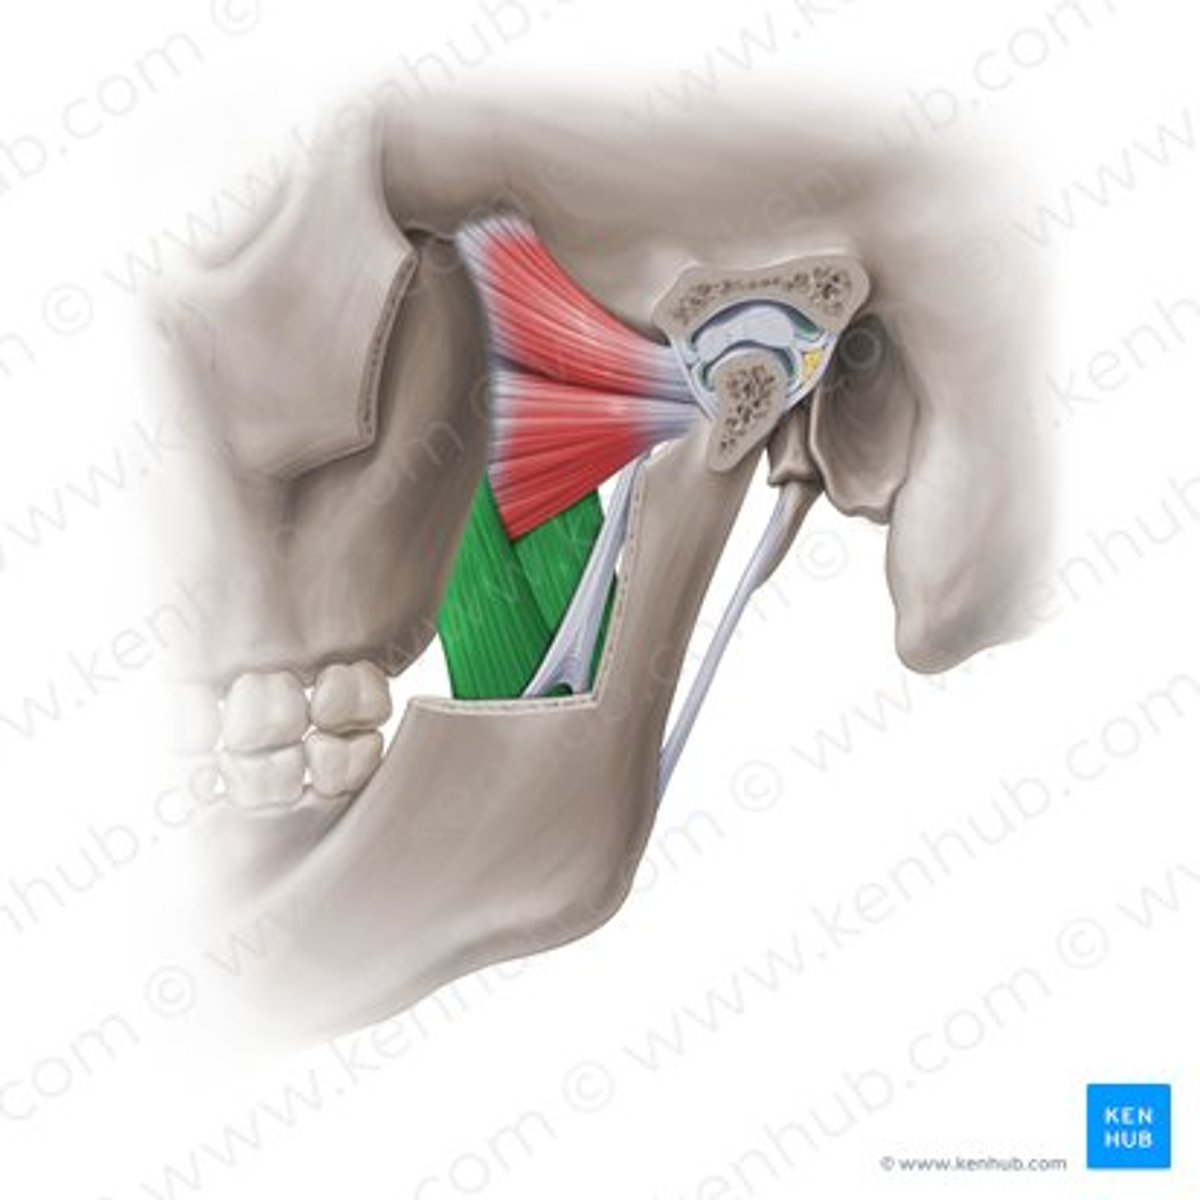

deep masseter

superficial masseter

temporalis

temporomandibular joint capsule

lateral pterygoid

lateral pterygoid, superior part

lateral pterygoid, inferior part

articular tubercle

head of mandible

articular disk

joint capsule